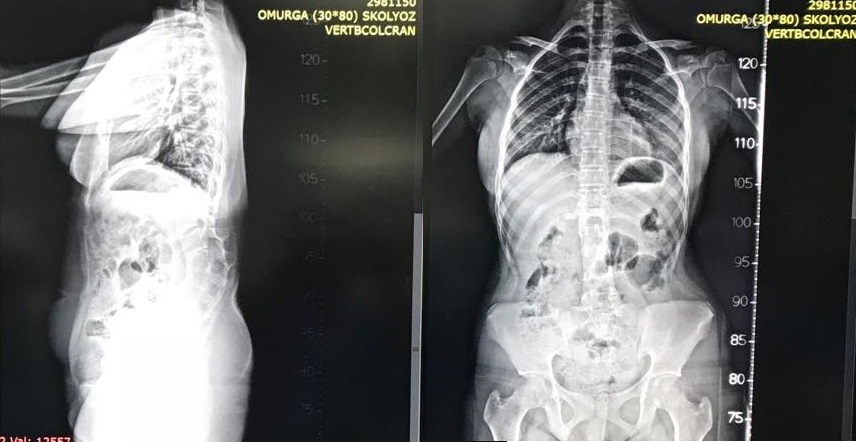

Lomber osteotomi yapıldı.

Ameliyat Görüntüleri